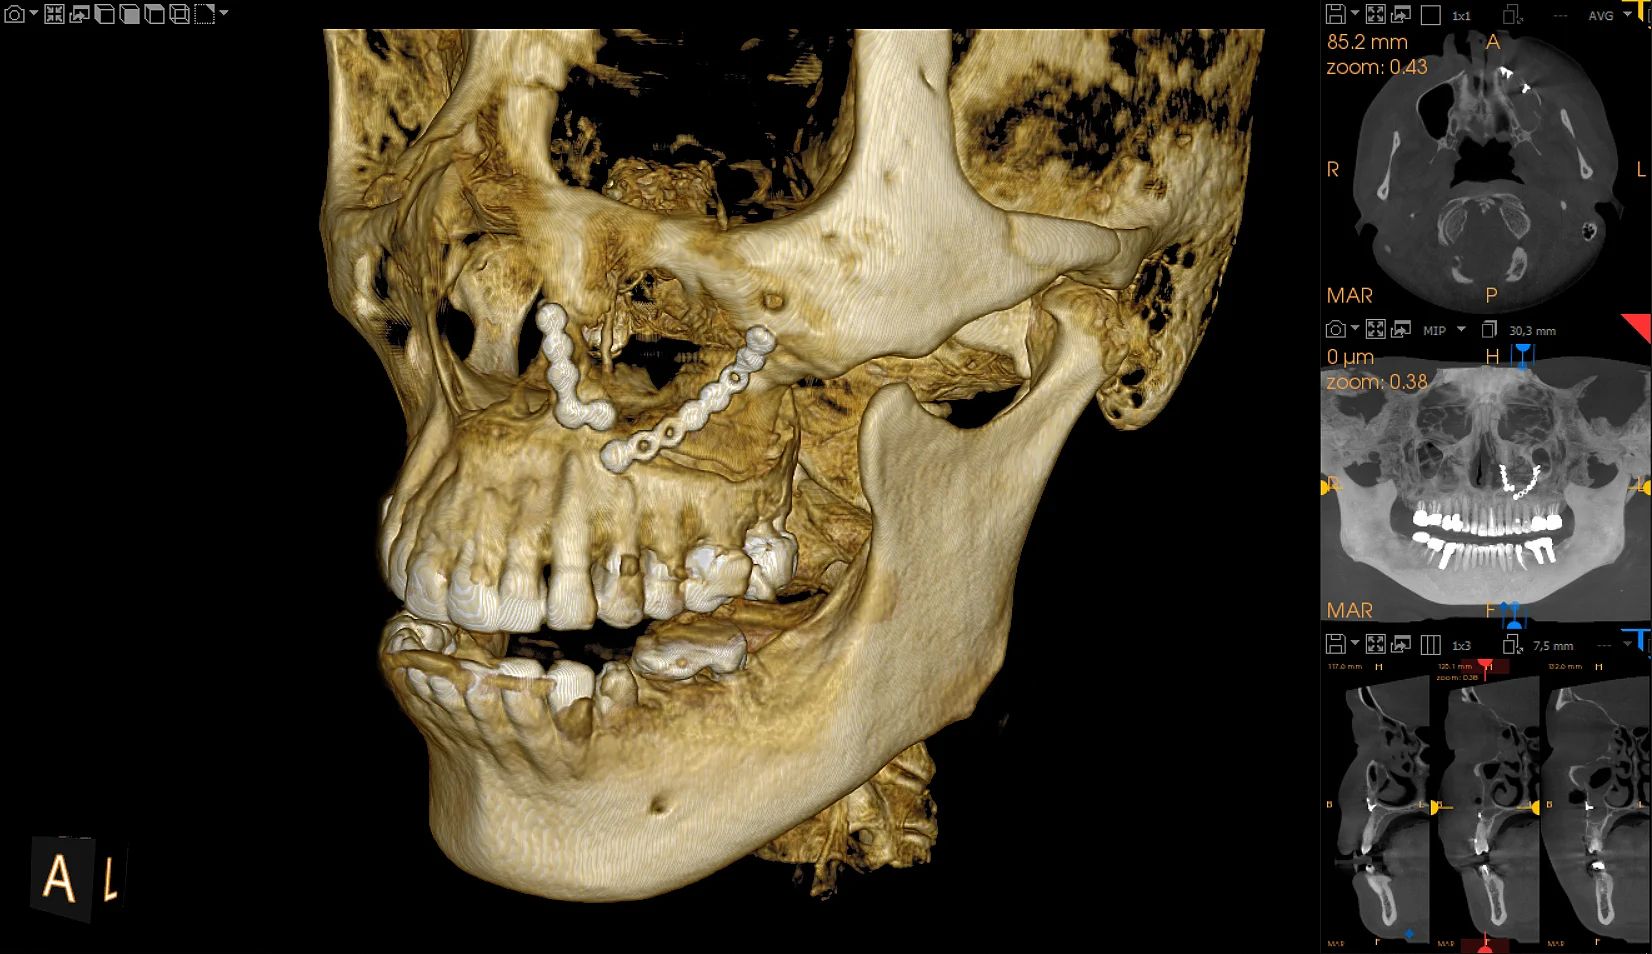

The CS 9600 features breakthrough innovations such as its artificial intelligence (AI)-powered positioning, video cameras, and Live Positioning Assistant to help enable users to produce high-quality images.

“The 5-in-1 CBCT scanner with extraordinary precision.”

"The Swiss Army Knife of diagnostic capabilities.” – Paul Feuerstein, DMD